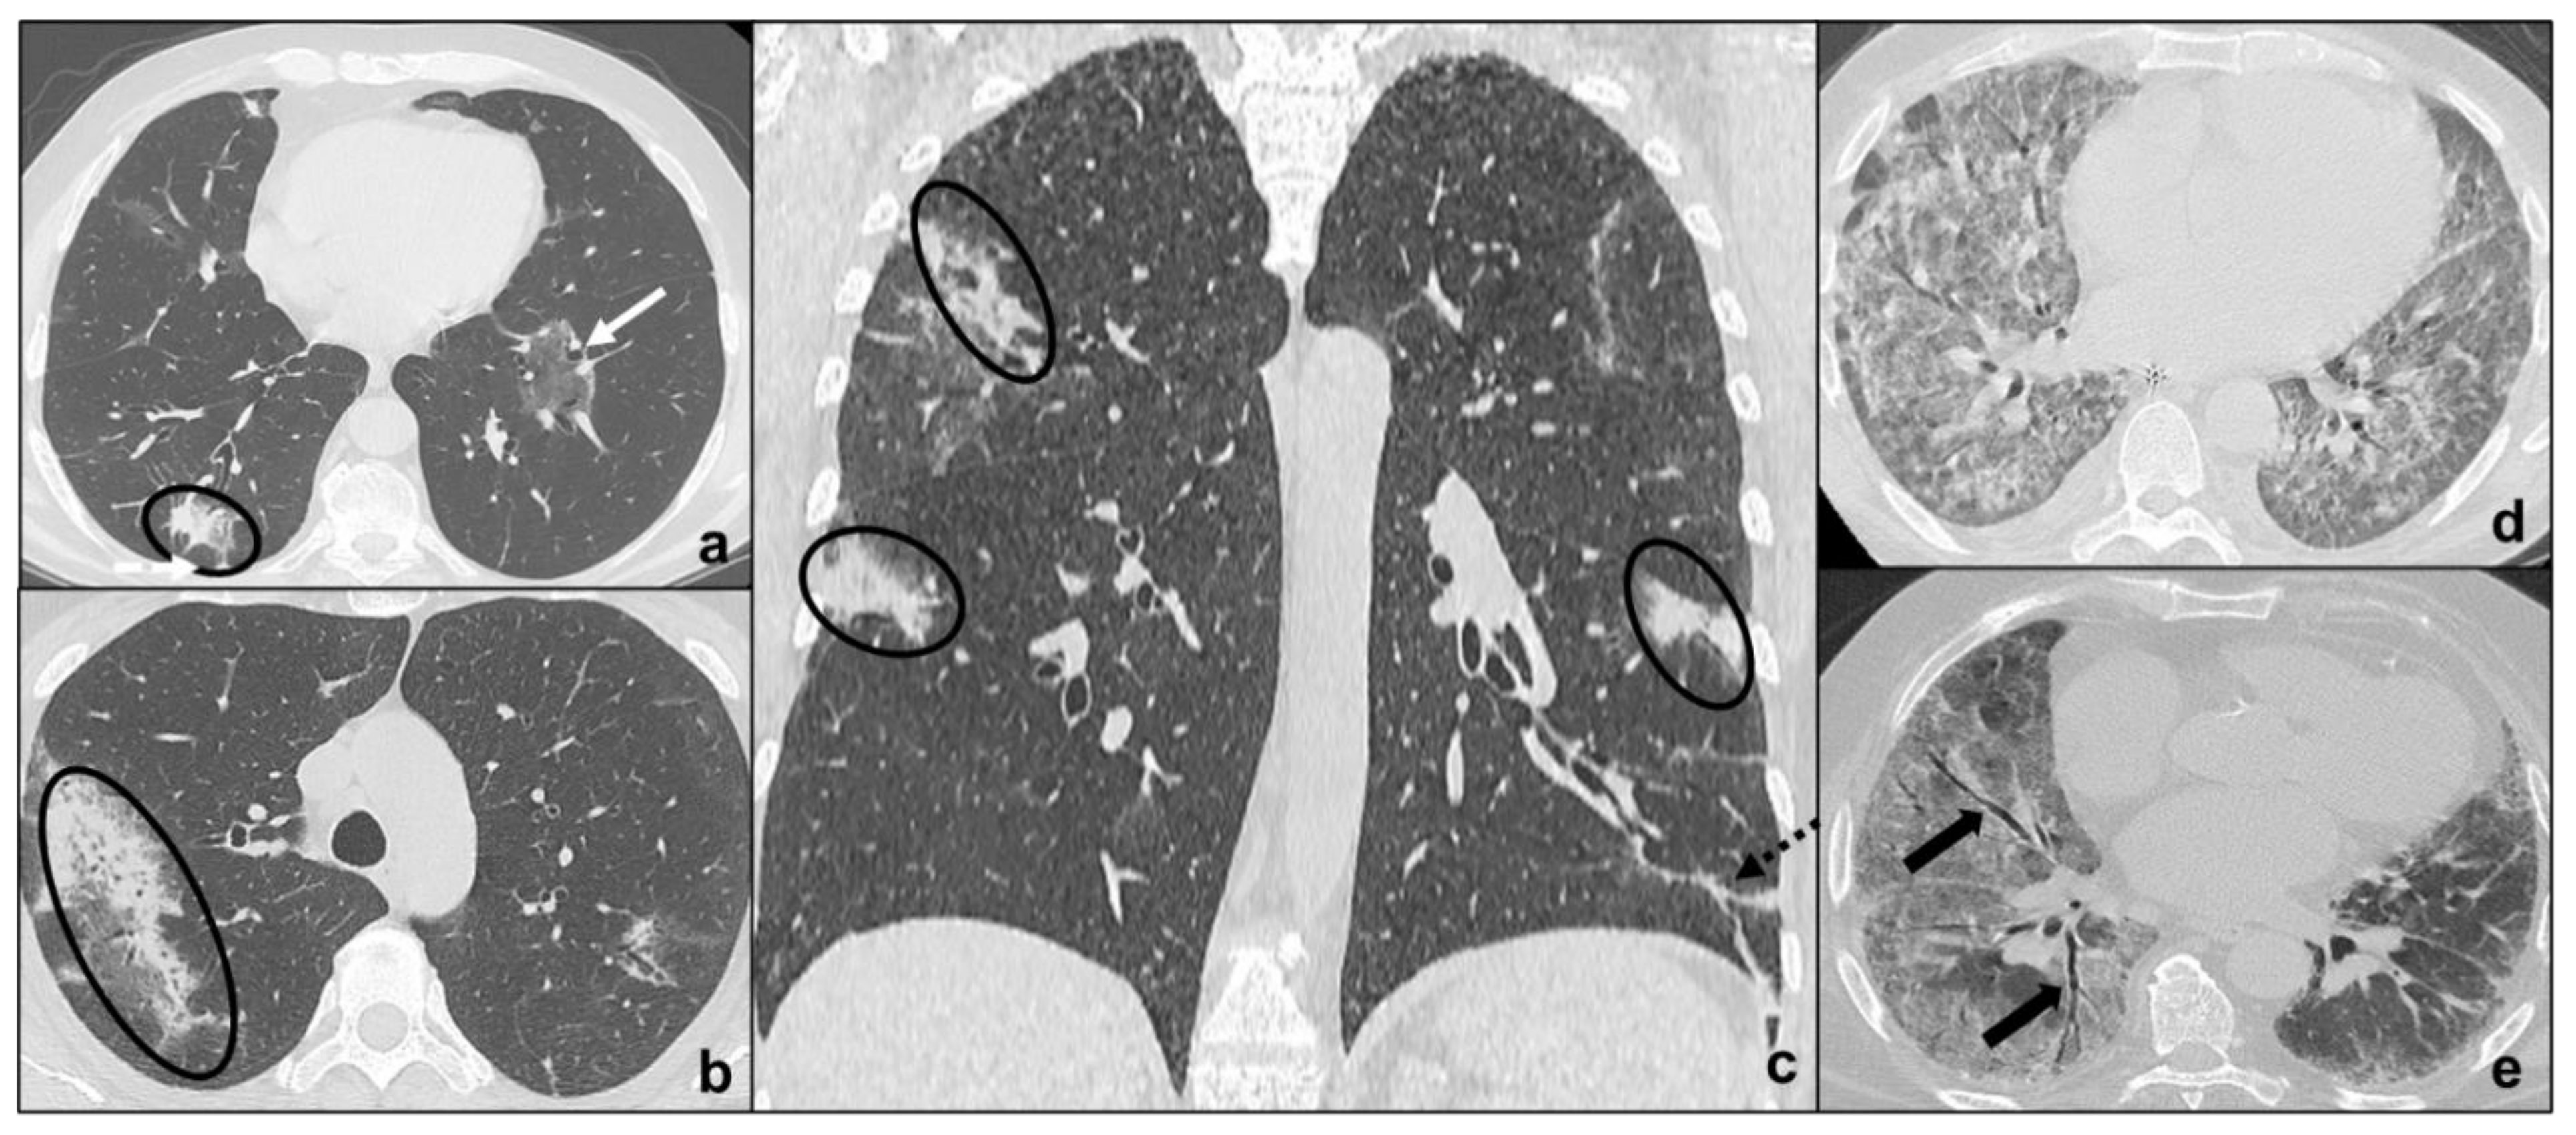

Figure 5.

Major IIPs: Acute/Subacute IIPs. In (a–c), OP shows centro-parenchymal ground glass opacities (black arrow in (a)) coexisting with consolidations (black circles in (a–c)) and is characterized by typical subpleural parenchymal preservation (white dotted arrows in (a)), and irregular consolidations (black dotted arrow in (c)). In (d), exudative AIP is indicated by confluent, symmetric ground-glass opacities, and smooth septal thickening; while, in e, organizing AIP is characterized by architectural distortions, traction bronchiectases (black arrow in (e)), and microcystic honeycombing (white circle in (e)) coexisting with ground-glass opacities and consolidative foci.

OP may be idiopathic (COP) or secondary to collagenopathies, pneumotoxic drugs, cancer, or vasculitis and represents a stereotypical pulmonary reaction. OP presents with cough and dyspnea, which worsen during exacerbations and may be accompanied by fever [44]. In the initial stage, HRTC shows unilateral or bilateral patchy ground glass opacities evolving to consolidations with air bronchogram, surrounded by ground glass (reversed halo sign) in the late stages [45]. There is an apicobasal gradient with peribronchial or peripheral distribution [46]. In some cases, subpleural pulmonary tissue is spared [47,48]) similarly to NSIP and differently to UIP. OP opacities characteristically migrate, changing location and size; and increase over weeks of antibiotics [47]. Centrilobular nodules may be present and cavitate or coexist with irregular linear opacities [49,50] (Figure 5a–c). OP exacerbations may result in progressive interstitial fibrosis and represent a fibrosing variant of OP resembling NSIP [5]. Differential diagnosis between the two IIPs is suggested by the presence of consolidations in OP [5], although NSIP and OP may overlap in lung-dominant connective tissue disease [51], as they represent a stereotypical pulmonary response to external or internal agents.

Acute Interstitial Pneumonia

AIP patients show sudden onset of dyspnea with laboratory alterations and frequently need hospital admission. It is a pneumonia consisting of two main phases. During the early stage (exudative AIP), bilateral, symmetric, patchy ground glass opacities are predominant and may coexist with consolidations of the dependent segments of the lungs [52,53]. Then, in the late phase (organizing AIP), architectural distortions, traction bronchiectases, and honeycombing are common findings [54,55] (Figure 5d,e). Organizing AIP may progress to other IIP patterns as NSIP or to pulmonary fibrosis [56,57].

It is a rare IIP presenting with cough and dyspnea and is not rarely associated with systemic immunodeficiency syndromes [5]. Chest CT demonstrates diffuse and basal ground glass opacities, centrilobular nodules, and septal thickening [35]. The hallmark of LIP is the presence of thin-walled perivascular cysts disseminated through the lung parenchyma with bilateral perivascular distribution [60] in contrast to UIP (Figure 6a).

Rare IIPs. In (a), LIP is characterized by thin-walled perivascular cysts (white-bordered black arrows in (a)), and may coexist with subpleural ground glass opacities (white arrow in (a)) and crazy paving pattern (black arrow in (a)); in (b), PPFE is characterized by architectural distortions, traction bronchiectases, and subpleural fibrotic consolidations distributed bilaterally and predominantly at the upper fields.

3.2.2. Idiopathic Pleuroparenchymal Fibroelastosis

PPFE is a rare IIP presenting with dyspnea and cough and associated with bone marrow transplantation, autoimmune disease, and genetic predisposition. PPFE is characterized by bilateral, subpleural fibrotic changes and pleural thickening, resulting in dense subpleural consolidations coexisting with architectural distortions, traction bronchiectasis, and hilar elevation leading to progressive upper lobe volume loss [5,32,61]. It shows upper field predominance, and pneumothorax is a common complication [5] (Figure 6b).